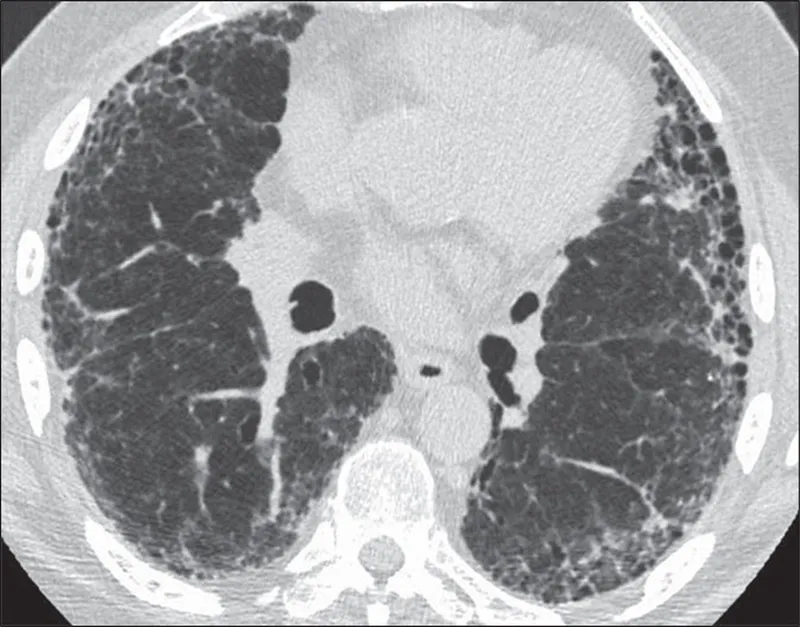

- Honeycombing: Clustered, stacked subpleural cysts (typically 3-10 mm diameter, <3 mm walls); key for UIP.

⭐ Honeycombing on HRCT is a hallmark of the Usual Interstitial Pneumonia (UIP) pattern, indicating irreversible fibrosis and generally associated with a poorer prognosis compared to other IIPs without honeycombing.

- UIP Pattern (HRCT): Basal, subpleural, reticular pattern; honeycombing is hallmark. +/- traction bronchiectasis. Absence of features suggesting alternative diagnoses.

⭐ Honeycombing on HRCT is the most specific finding for a UIP pattern.

- UIP/IPF: Characterized by basal, subpleural honeycombing.